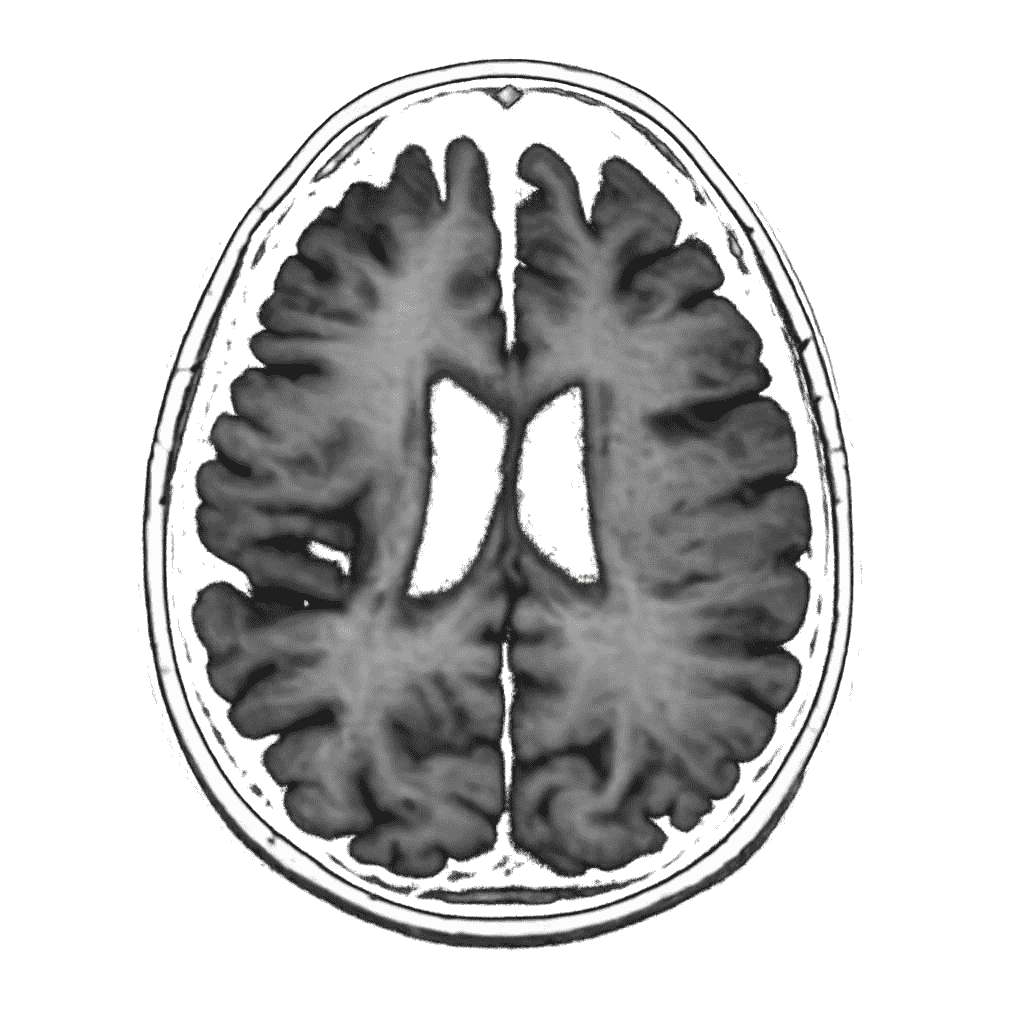

In Ayurveda, brain atrophy is understood as a condition involving Vata dosha aggravation along with depletion of Ojas, the vital essence responsible for mental resilience, immunity, and neurological strength. The deterioration of higher mental faculties Dhi (intellect), Dhriti (retention), and Smriti (memory) is central to this condition. Weak Agni (digestive fire), chronic inflammation, oxidative stress, ageing, and impaired circulation lead to accumulation of Ama (metabolic toxins), obstructing subtle channels (Nadis) that nourish the brain and spinal system. Ayurvedic care focuses on pacifying Vata, enhancing Ojas, nourishing nerve tissues, and supporting long-term cognitive stability.